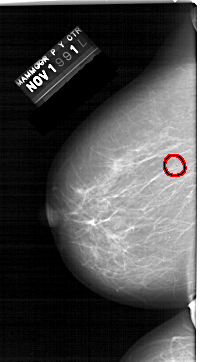

A_1324_1.LEFT_MLO

LEFT_MLO LINES 6466 PIXELS_PER_LINE 3811 BITS_PER_PIXEL 12 RESOLUTION 43.5 OVERLAY

FILE: A_1324_1.LEFT_MLO.OVERLAY

TOTAL_ABNORMALITIES 1

ABNORMALITY 1

LESION_TYPE CALCIFICATION TYPE PLEOMORPHIC DISTRIBUTION CLUSTERED

ASSESSMENT 4

SUBTLETY 3

PATHOLOGY BENIGN

TOTAL_OUTLINES 1

BOUNDARY